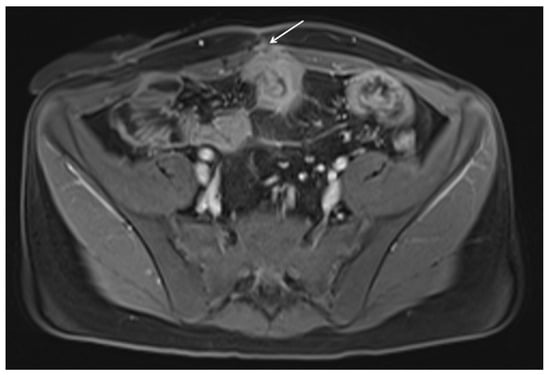

11. Imaging Findings Associated with Penetrating CD Inflammation and Complications

Fistula

| Abscess |